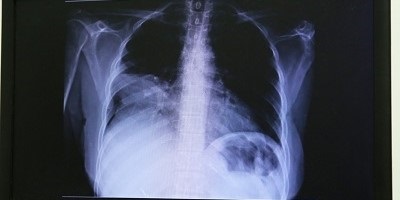

Una intervención temprana que promovemos en el Issste, indicó, es la realización de una placa de tórax a personas con factores de riesgo, estudio que puede salvar vidas, ya que 90 por ciento de los cánceres de pulmón se diagnostican inicialmente a través de este estudio de imagen.